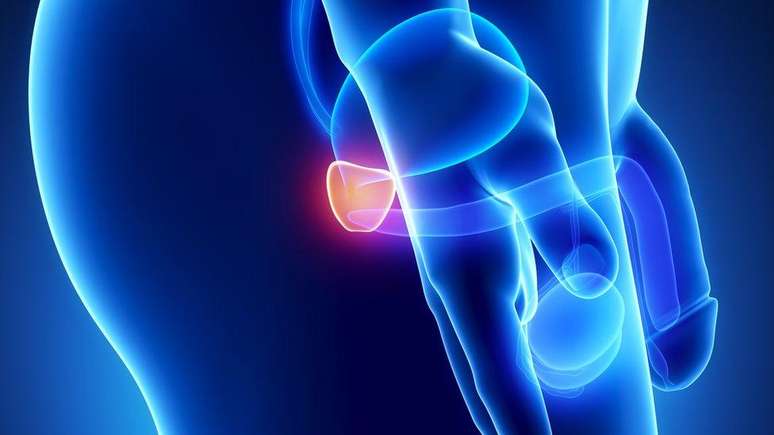

A próstata é uma glândula do tamanho de uma noz. Ela fica na pélvis e rodeia a uretra quando ela sai da bexiga. Convenientemente, ela fica ao lado do reto e é facilmente percebida pelo dedo durante o exame.

A próstata fica localizada entre o reto e a base do pênis

Foto: Getty Images / BBC News Brasil